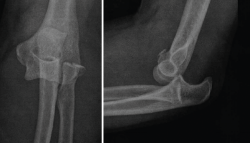

Figura 5. Radiografías simples de codo en proyección anteroposterior y lateral. En estas radiografías puede apreciarse una luxación posterolateral de un codo izquierdo, además de fractura de la cabeza del radio y fractura de la punta de la coronoides.

3. Radiografías simples de codo en proyección anteroposterior (AP) y lateral (Figura 5).